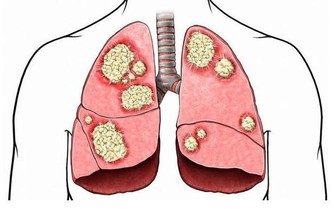

呼吸

健康人呼吸平穩、規律,每分鐘15次左右,

如發現呼吸的深度、頻率、節律異常,呼吸費力、有胸悶、憋氣感受,則為不正常表現,應就醫。

呼吸增快主要見於肺炎、肺栓塞、胸膜炎、支氣管哮喘、充血性心力衰竭、代謝亢進以及神經精神障礙等。